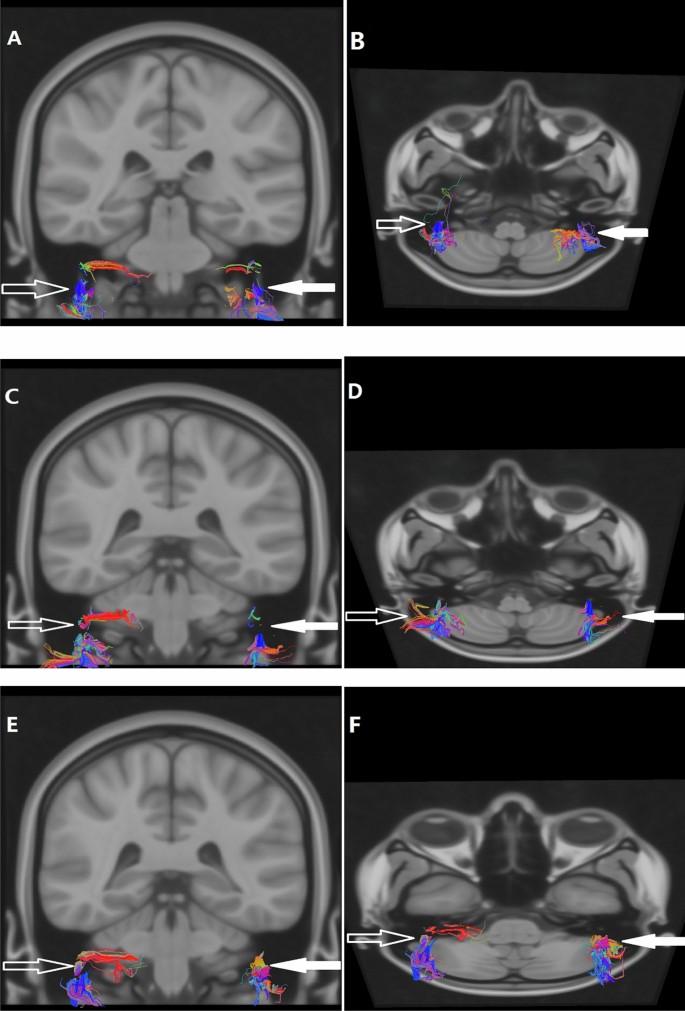

After eddy, current correction of the DTI data, affine transformation, and nonlinear matching were performed on the diffusion images matching with the MNI152_T1_0.4 mm template without skull-stripping by using the FSL (Oxford, UK). Then the voxel size of the DTI was resampled to 0.4 mm3 in the common space of the MNI152_T1_0.4 mm template. DTI data were used to track each intratemporal facial nerve fiber in 0.4 mm3 common space by using TrackVis and its Diffusion Toolkit (DTK). The intratemporal facial nerve fibers were traced with a threshold value of FA > 0.15 and an angle threshold value of 60°. To reduce errors, the step length of fibers less than 2 mm was discarded (Fig. 3).

DTI fiber tracing of bilateral intratemporal facial nerves was performed. A patient (A, B) is a female, 46 years old, with right facial paralysis for 3 days and H-B facial nerve function grade IV. A patient (C, D) is a male, 23 years old, with right facial paralysis for 7 days and H-B facial nerve function grade III. A patient (E, F) is a male, 59 years old, with left facial paralysis for 1 day and H-B facial nerve function grade III. The left (solid arrow) and right (hollow arrow) intratemporal facial nerves were indicated by the arrows respectively.